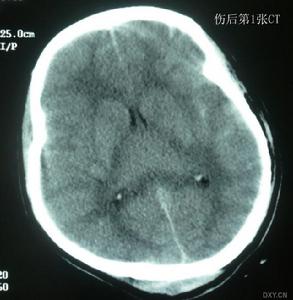

2、CT掃描檢查可以看到確切的損傷部位和範圍,並能對異物或骨片的位置、分布作出精確的定位。特別是當顱內繼發血腫、積液或後期的腦積水、腦腫脹、腦穿通畸形及癲癇病灶均有重要診斷價值。

2、顱腦CT掃描可顯示顱骨、腦組織的損傷情況,更重要的是能夠準確地對碎骨片及異物定位,發現顱內或腦內血腫等繼發性改變。CT較X線平片更能清楚地顯示X線吸收係數低的非金屬異物。